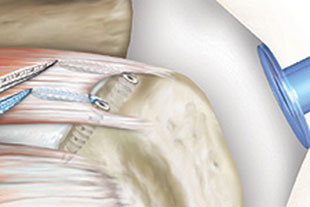

Ablauf einer beispielhaften Naht der Rotatorenmanschette

Einbringen eines Fadenankers in den Oberarmkopf

Versenken des Fadenankers unter der Knochenoberfläche

Einbringen des am Anker befestigten Fadens in die Sehne

Einbringen eines 2. Fadenankers und eines 2. Fadens in die Sehne

Zug der Sehnenplatte über die eingebrachten Fäden zum ursprünglichen Ansatzpunkt der Sehne

Einbringen eines weiteren Ankers zur Fixierung der Fäden und somit der Sehnenplatte am ursprünglichen Ansatzpunkt

Einbringen eines 4. Ankers und Fixierung der überkreuzten Fäden zur optimalen Stabilisierung der Rotatorenmanschette am Oberarmknochen

Alle Bilder der Rotatorenmanschettennaht mit freundlicher Genehmigung der Firma Arthrex®